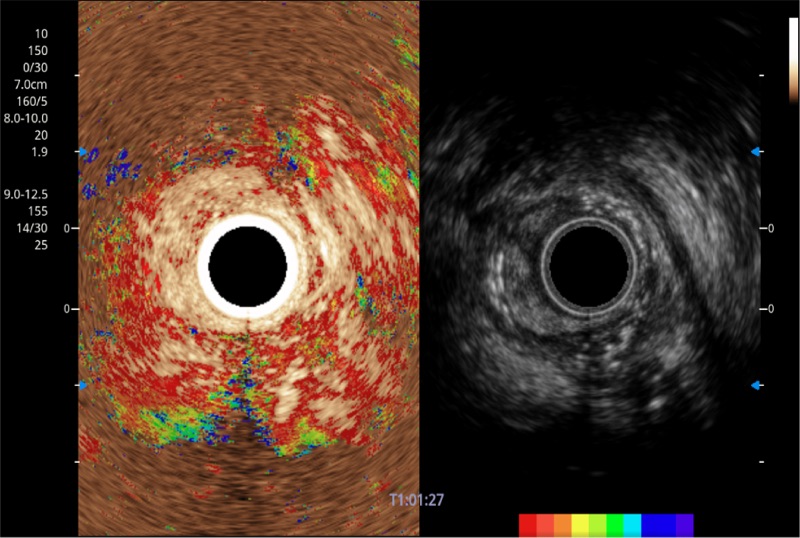

可人为将灰阶图像转变成彩色的显示方式,增强人眼对于不同回声强度的敏感度,主观上增加了图像分辨率

食管内间质瘤清晰显像

清晰显示胆总管及周围血管分布

肝左叶和肝静脉的横截面